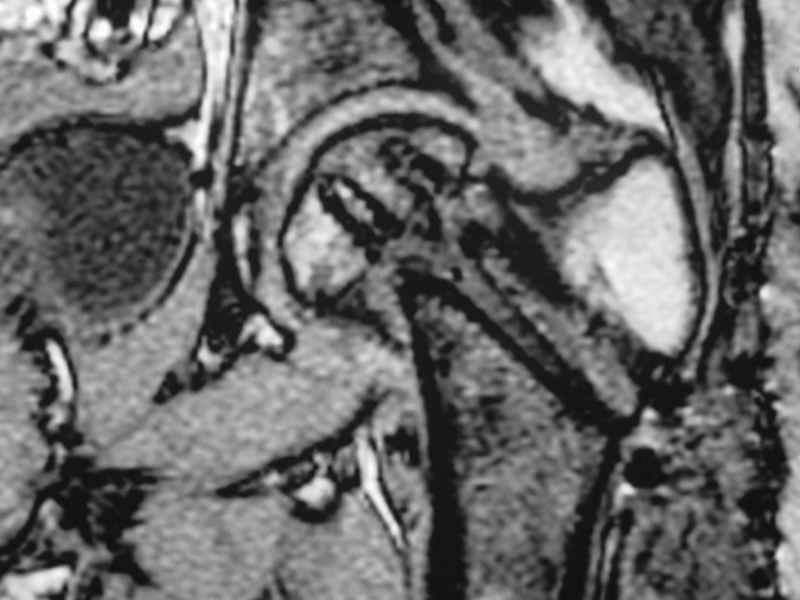

Erden K?l?c 16 Октябрь 2005, 00:03

I would leave it as it is. Because surgical intervention will not be able to prevent osteonecrosis if it is going to be. MRI may be helpful to determine union if there is any and also gives an idea about the viability of the head.

Erden K?l?c, MD

Stephen Kottmeier 17 Октябрь 2005, 21:05

friend

dhs will not correct improper biomechanical environment and may further compromise vascular

integrity consider establish vascular status via mri